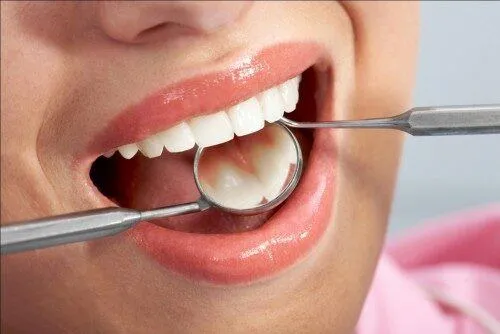

Nhổ răng là một thủ thuật nha khoa giúp loại bỏ răng bị hư hỏng hoặc có vấn đề ra khỏi miệng. Trước khi thực hiện, bác